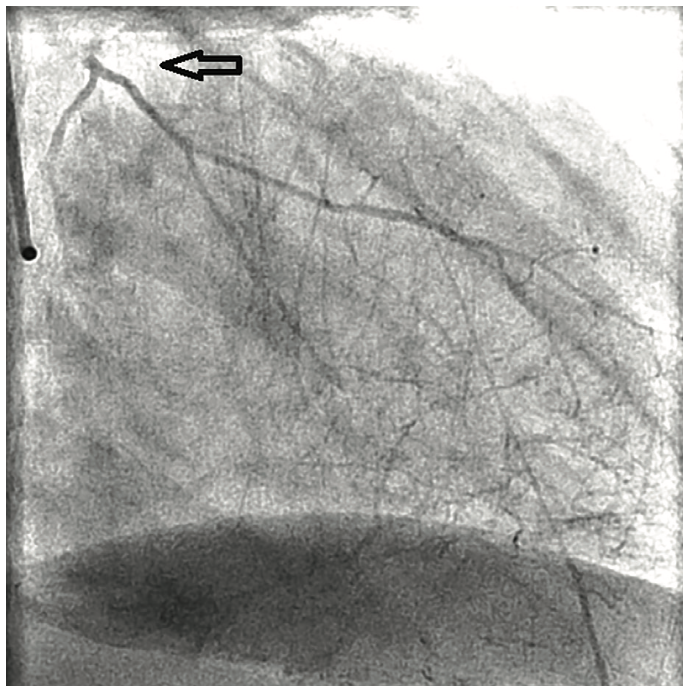

Angiographic findings of atherosclerotic disease and stenosis in the left main coronary artery are not uncommon in both symptomatic and relatively asymptomatic patients. However, the angiographic finding of a completely occluded left main coronary artery is relatively uncommon and most often not compatible with life.1,2 It is even more unusual to have no symptoms related to the complete obstruction of the left main coronary artery.

Left main coronary artery stenosis to a varying degree is not an uncommon finding on coronary angiography in patients with known and unknown coronary artery disease. Several reports and studies have been published pertaining to clinical presentation and management of left main coronary artery stenosis, but very little is known about the clinical presentation or incidence of left main coronary artery occlusion. This is likely due to total occlusion of the left main coronary artery being incompatible with life. Total occlusion of the left main coronary artery is usually a highly symptomatic event or in many cases, a terminal event. The survival rate and clinical symptoms are likely correlated with the rate of occlusion and the degree of collateralization from the right coronary artery that can supply blood flow to the left coronary arteries when the left main coronary artery becomes totally occluded.